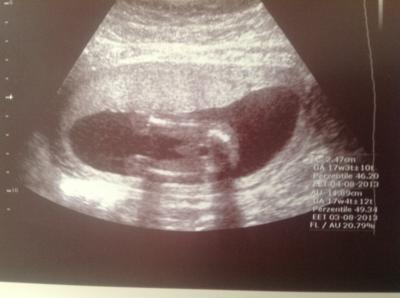

Hallo Mädels, war heute normal zur Vorsorge und habe einen Ultraschall machen lassen für 30€. Alles soweit in Ordnung! Es wird ein Junge! :-))) Bin sofort in die Firma Gefahren um meinem Schatz das Ergebnis mitzuteilen, er hat gefreut wie ein Keks! Ich bin happy! Beweisfoto anbei! Liebe Grüße Dörte

wie süss... die beinchen und der po glückwunsch zu euren sohn :)